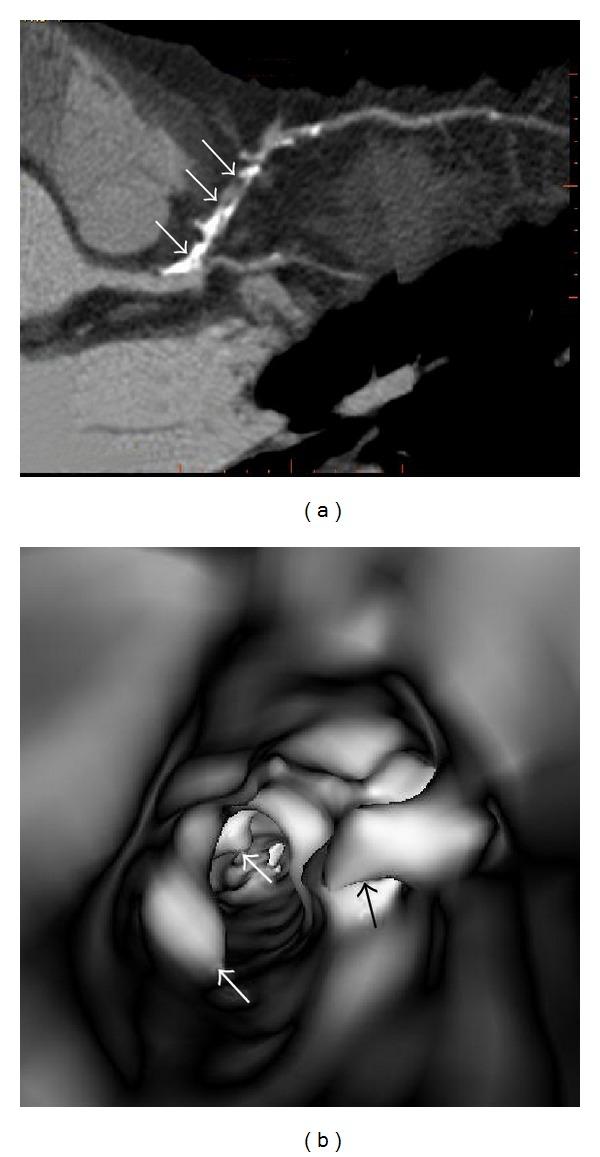

Coronary computed tomography angiography (CCTA) has been recently evaluated for its ability to assess coronary plaque characteristics, including plaque composition. Identification of the relationship between plaque composition by CCTA and patient clinical presentations may provide insight into the pathophysiology of coronary artery plaque, thus assisting identification of vulnerable plaques which are associated with the development of acute coronary syndrome. CCTA-generated 3D visualizations allow evaluation of both coronary lesions and lumen changes, which are considered to enhance the diagnostic performance of CCTA. The purpose of this review is to discuss the recent developments that have occurred in the field of CCTA with regard to its diagnostic accuracy in the quantitative assessment of coronary plaques, with a focus on the characterization of plaque components and identification of vulnerable plaques.

冠状动脉计算机断层扫描血管造影(CCTA)最近已就其评估冠状动脉斑块特征(包括斑块成分)的能力进行了评估。确定CCTA显示的斑块成分与患者临床表现之间的关系,可能有助于深入了解冠状动脉斑块的病理生理学,从而有助于识别与急性冠状动脉综合征发生相关的易损斑块。CCTA生成的三维可视化图像可用于评估冠状动脉病变和管腔变化,这被认为可提高CCTA的诊断性能。本综述的目的是讨论CCTA领域在冠状动脉斑块定量评估诊断准确性方面的最新进展,重点是斑块成分的特征描述和易损斑块的识别。